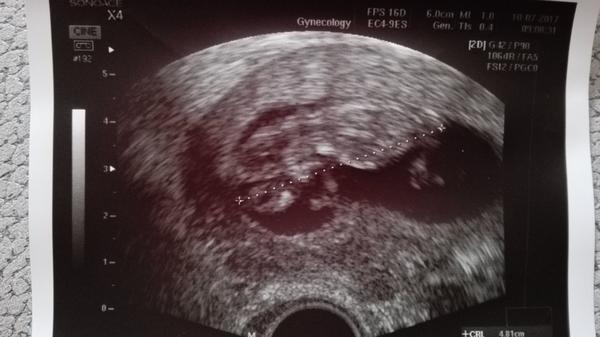

Zdravím, já jsem dnes už 18. den po ET, těhu už mám potvrzené předevčírem z krve (4525j. hcg) a včera od svého gyndaře ultrazvukem 🙂 slabou čárku jsem měla taky od 6. dne po ET, akorát já měla jistotu, že to není po injekci, protože jsme měli darované vajíčko.

@yetti130 držím palce. Klidně hod fotecku tu my rádi ze holky